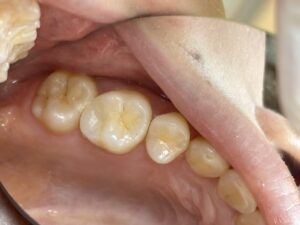

歯の神経を取る根の治療 根管治療をすれば治ります。治した後は 保険適応でハイブリッドセラミックやCAD/CAM冠インレー クラウンなどで白い歯で治すといいですね。もちろんセラミックやジルコニアの治療もあります。